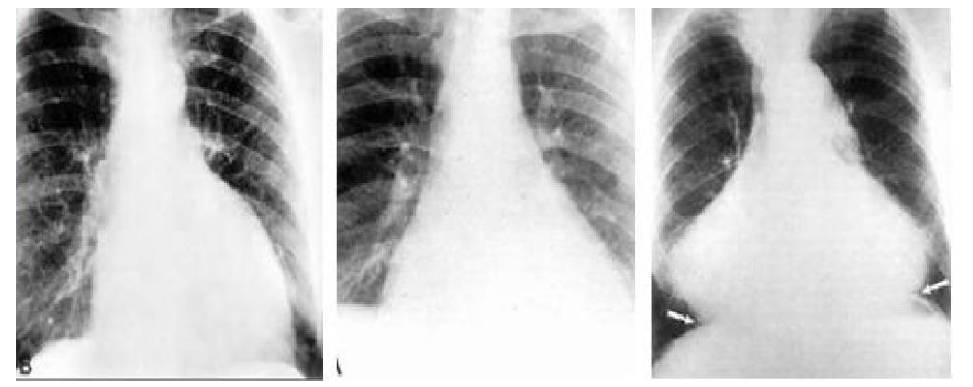

一般X线表现

♦1.积液<300ml:心影无明显改变

♦2.积液>300ml:

(1)当心包积液量大300-500ml,心影开始向两侧增大,并有上腔静脉影增宽及心膈角变钝的表现

(2)当心包积液超过1000ml,心影明显增大呈“烧瓶状”或“球形”,各心弓界限不清,心膈角变锐

(3)肺纹理正常或减少,肺野清晰

(4)短期内几次X线片出现心影迅速扩大

(5)上纵隔影短缩

(6)心脏搏动减弱或消失